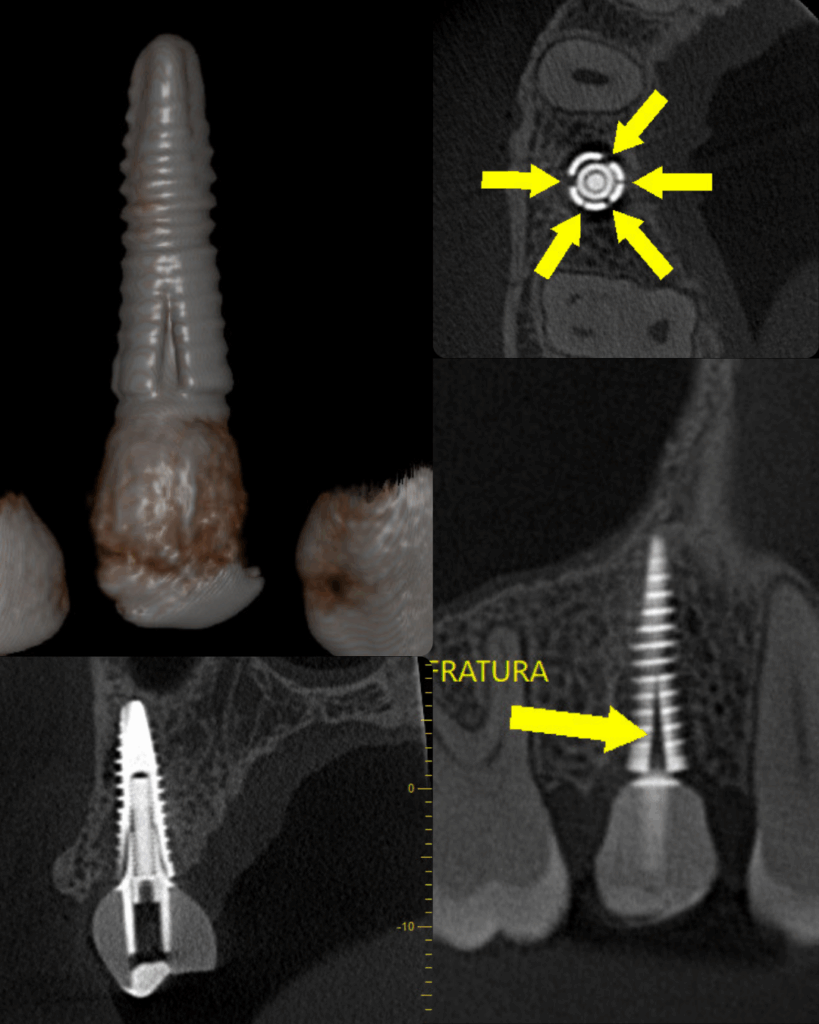

Ela possibilita obter informações detalhadas sobre os dentes, ossos, tecidos moles e articulações. Com isso, é possível identificar com precisão fraturas dentárias, lesões ósseas, infecções, cistos, tumores e problemas em estágios iniciais, proporcionando um diagnóstico precoce e eficaz.

Detecção de Lesões Ocultas e Microfraturas

Capaz de identificar pequenas lesões e fraturas que não são visíveis em radiografias convencionais, garantindo um diagnóstico mais abrangente.